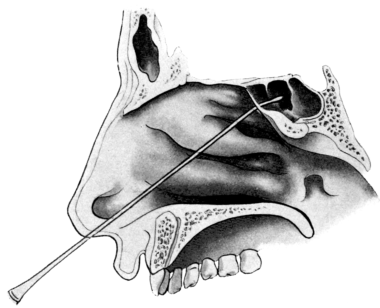

| 345. | Catheterizing the Sphenoidal Sinus | 654 |

| 347. | Radiograph showing a Probe in the Sphenoidal Sinus | 657 |

| 333. | Catheterizing the Frontal Sinus | 639 |